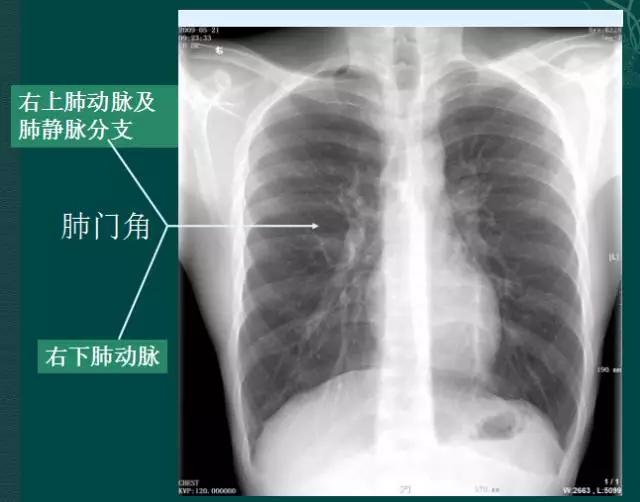

4、肺门的大小和位置

x线肺门指肺动脉、肺叶动脉、肺段动脉、伴行支气管以及肺静脉构成。

右肺门可分为上、下两部。上部约占1/3,由上肺静脉、上肺动脉及下肺动脉后回归支构成。上肺静脉下后干构成右上肺门的外缘;右肺门下部 约占2/3,由右下肺动脉干构成,其正常宽度不超过15mm,沿中间段支气管外缘平行向外下走行。右肺门上、下部相交形成一钝的夹角,称肺门角,正常该角顶清晰。如下图

左肺门亦分为上、下两部。上部由左肺动脉及其分支、左上叶支气管和左上肺静脉及其分支构成;下部由左下肺动脉及其分支构成,常被心影所遮盖。